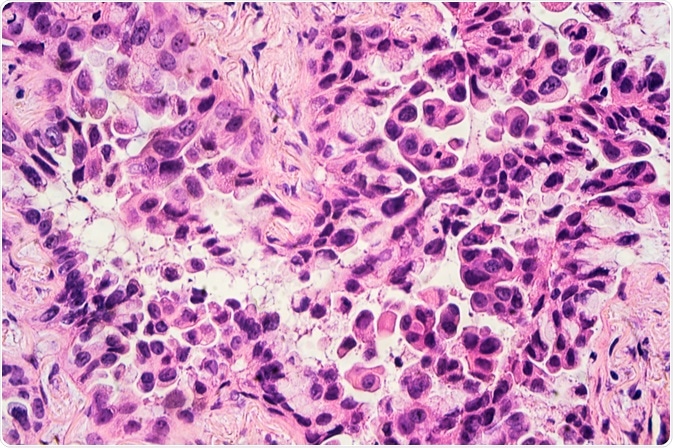

adenocarcinoma

Image Credit: David A Litman/Shutterstock.com

It is estimated that adenocarcinomas comprise approximately 40% of all lung cancers. By definition, adenocarcinoma in the lung is a malignant epithelial neoplasm that can be accompanied by either glandular differentiation or the production of mucin. Typically, an adenocarcinoma will form a peripherally located mass that exhibits both central fibrosis and pleural puckering.

Other gross appearances that can be associated with an adenocarcinoma diagnosis include a centrally located mass, diffuse lobar consolidation, multiple lobes distributed bilaterally, and pleural thickening.

Following a biopsy or tumor resection, an adenocarcinoma can be further characterized as a lepidic, acinar, papillar, micropapillary, solid, invasive mucinous, colloid, fetal, enteric, or minimally invasive carcinoma.